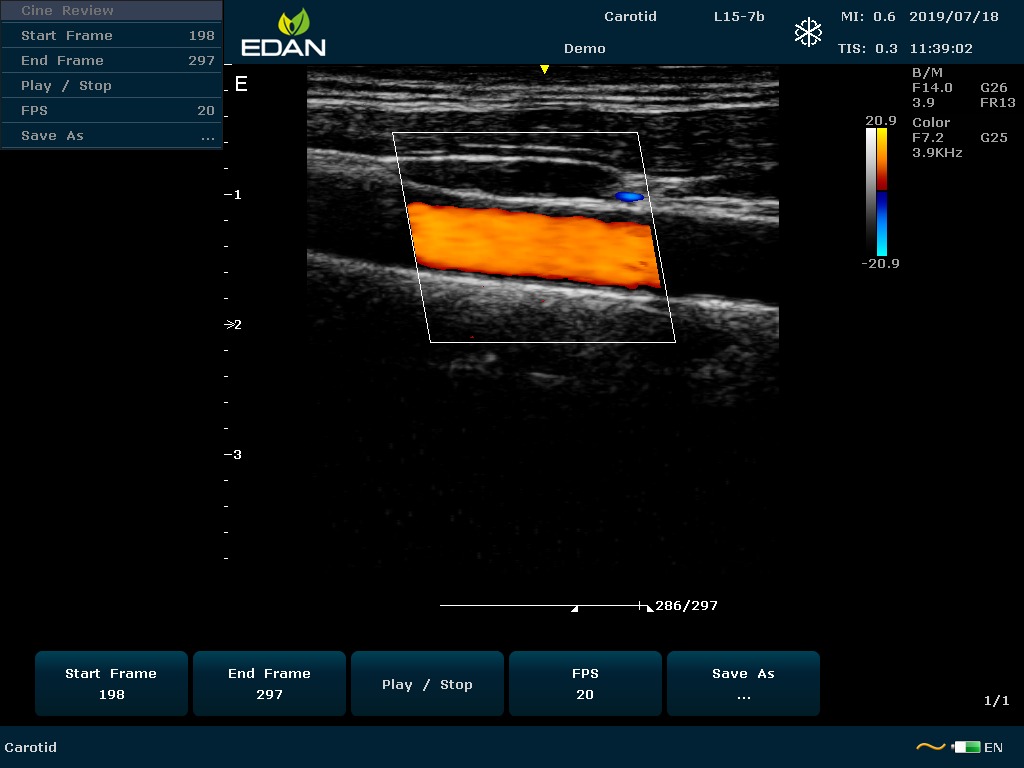

Особенность U60 Edan — расширенное применение. Ультразвуковой аппарат рекомендован для абдоминальных исследований, гинекологии и акушерства, кардиологии, педиатрии, урологии, изучения малых органов, сосудов. Для U60 Edan используются конвексные, линейные, фазированные и внутриполостные датчики.

Передовые технологии позволяют повысить качество визуализации в несколько раз. УЗИ-аппарат U60 Edan отличается возможностью быстрой настройки визуализации. Специальные функции позволяют моментально отображать данные за счет быстрой оптимизации параметров. Режимы визуализации: B-mode, M-mode, Color Doppler, Power Doppler Imaging, Pulsed Wave Doppler, Continuous Doppler.

• Цветовое Допплеровское картирование